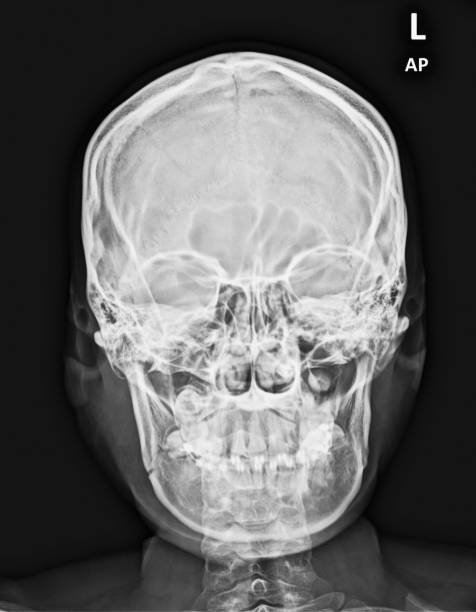

턱관절 장애는 말 그대로 턱과 관절에 문제가 있는 상태를 의미합니다. 이러한 상태는 오랜 기간 동안 축적되어 발생하며, 그 결과 다양한 증상이 나타날 수 있습니다.

- 비대칭 얼굴: 얼굴이 비대칭적으로 보일 수 있으며, 턱 관절 부분이 더 크거나 작게 보일 수 있습니다.